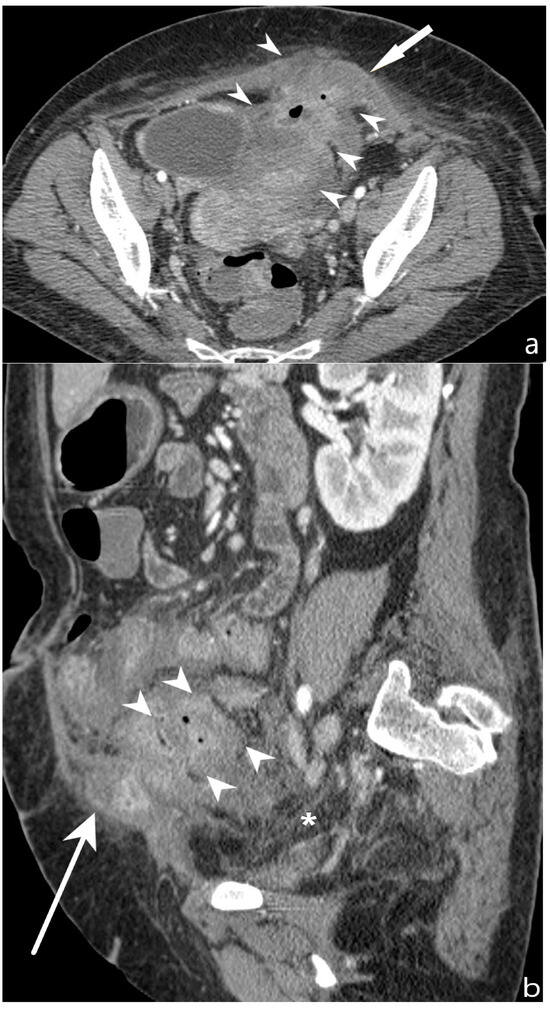

5.3. Fistulising/Perforating Subtype